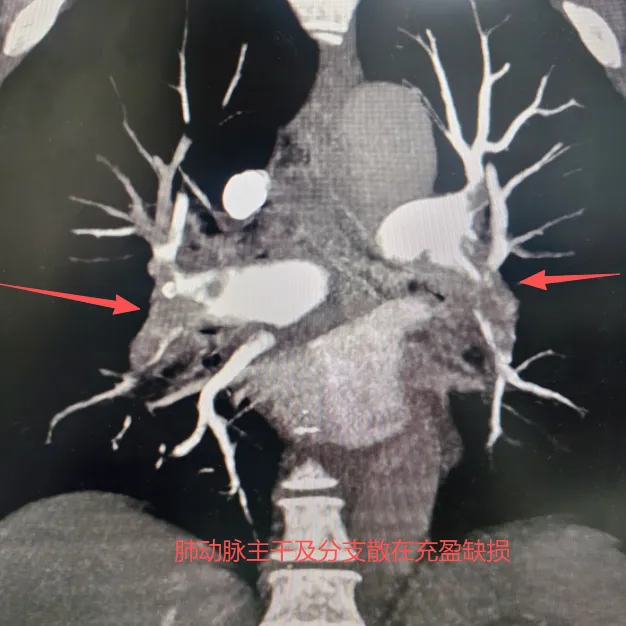

患者因“胸闷、气促10余天,加重1天”来院急诊。入院时指脉氧饱和度仅84%-86%,动脉血氧分压64mmHg,D-二聚体检测值高达13.74 mg/L FEU,提示身体存在严重的缺氧与血栓。病情危急,经紧急行下肢静脉超声及肺动脉CTA检查,最终确诊为“右下肢深静脉血栓形成伴双侧肺动脉主干及分支广泛栓塞”,生命危在旦夕。

影像科介入团队首先通过下肢静脉造影精确判断下肢仍有大量血栓存在,随后经左侧股静脉入路,成功置入下腔静脉滤器,如同设置一道“安全网”,有效预防了致死性肺栓塞的发生。紧接着,团队精准地将溶栓导管置入肺动脉主干,经导管注入尿激酶30万单位,并保留导管进行持续溶栓。术后,患者血氧饱和度显著提升,胸闷症状得到明显缓解。